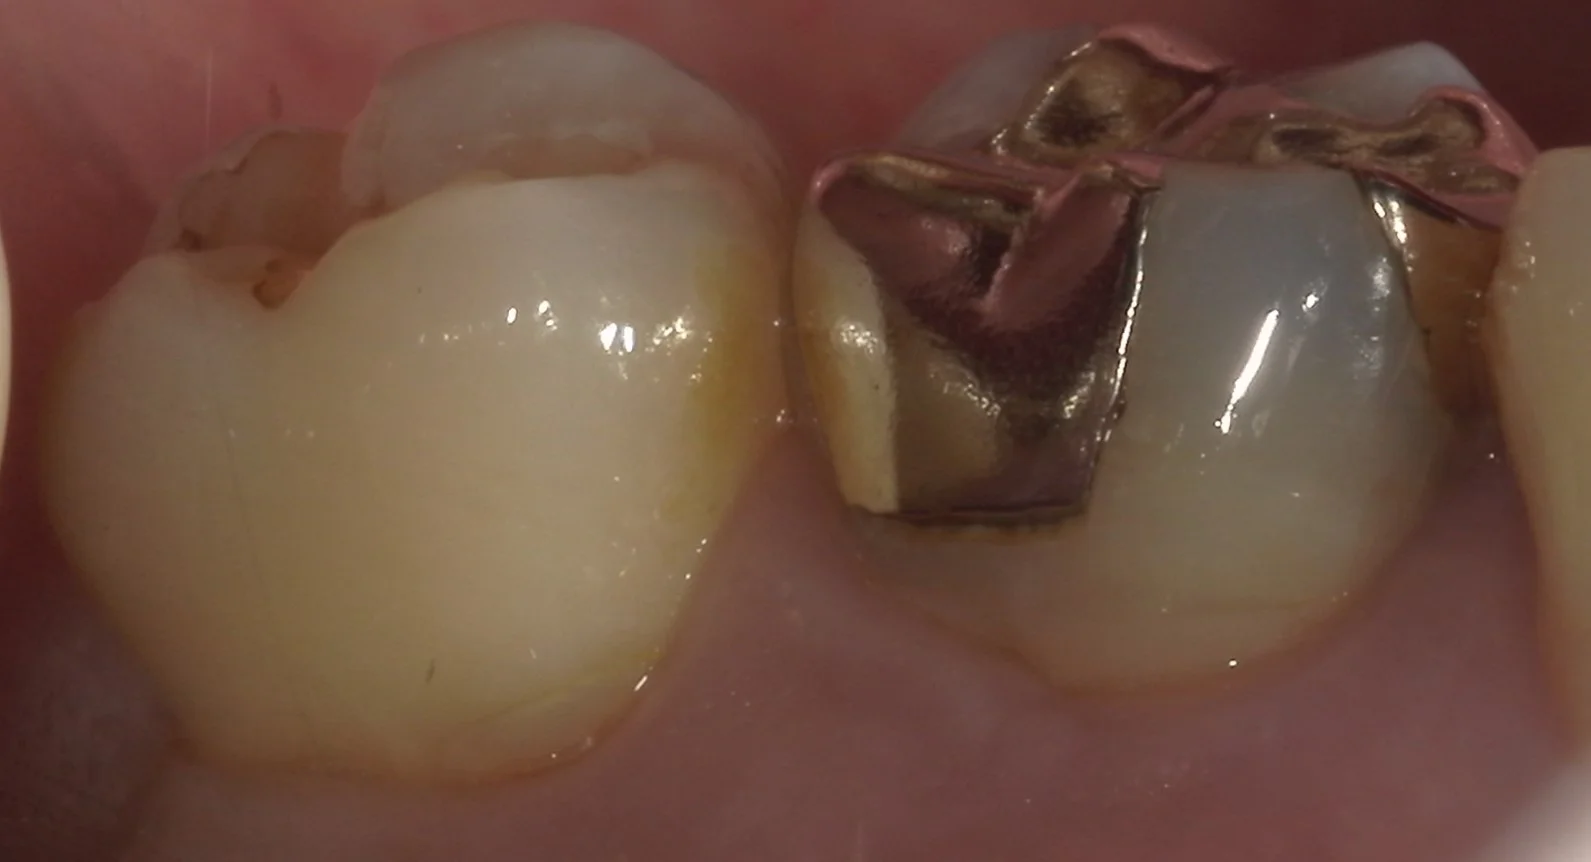

続いて、側面からの写真です。

歯の側面も同時に治療したケース。|坂寄歯科医院(取手市藤代) - 画像2

非常に広範囲に金属の詰め物が詰められているのが分かるかと思います。

また、歯茎の際辺りが歯ブラシの圧で抉れてしまっています。

こういった状態を「楔状欠損」と言い、実はダイレクトボンディングの中で治療が最も難しいと言われている状態になります。